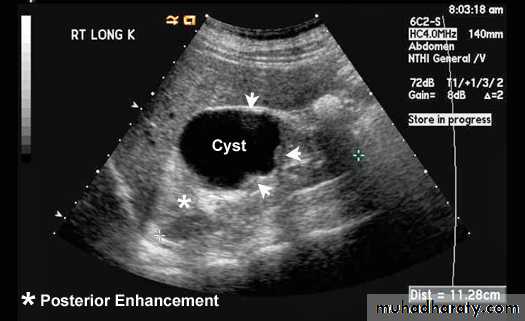

• Simple renal cysts• This represent the most common renal mass lesion.

• The incidence increasing with age and are present in

• 25-50% of subjects over the age of 50.

• These lesions are, by definition, simple with a thin

• wall and contain only serous fluid. They are found

• incidentally.

• On US: well demarcated, thin wall, homogenous fluid contents cyst with

• posterior acoustic enhancement.

• At CT: spherical mass with imperceptible wall, its contents are

• homogenous of fluid density (0 – 20 HU) with sharp margins